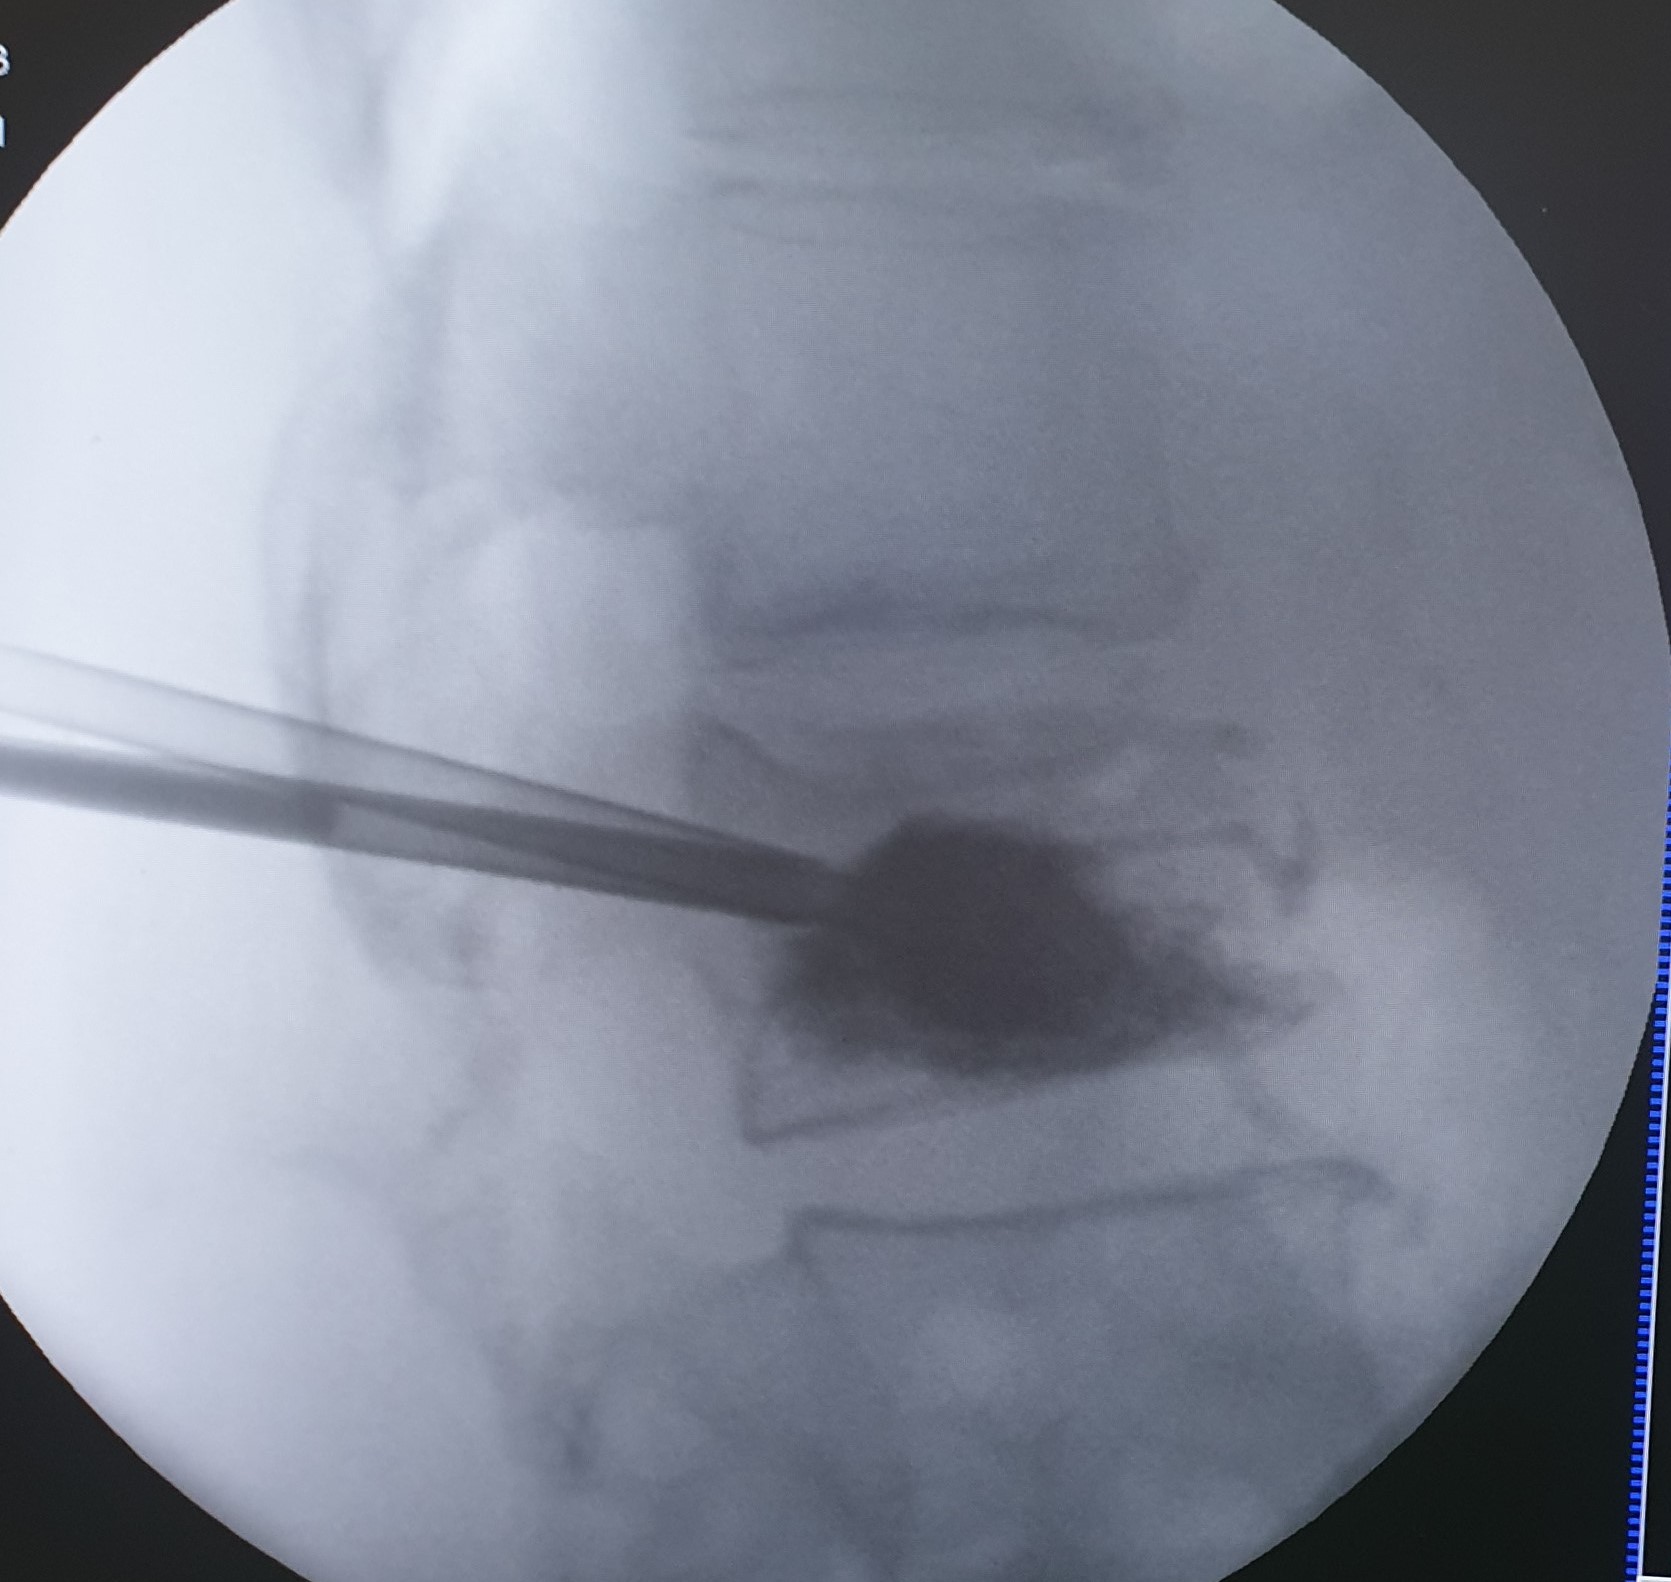

Η κυφοπλαστική και η σπονδυλοπλαστική αποτελούν ελάχιστα επεμβατικές τεχνικές αντιμετώπισης του πόνου που προκαλείται από συμπιεστικά καταγμάτα των σπονδύλων, επί εδάφους οστεοπόρωσης ή μεταστατικής νόσου. H προσπέλαση και στις δύο περιπτώσεις γίνεται διαδερμικά και κάτω από συνεχή ακτινοσκοπική καθοδήγηση.

Η κυφοπλαστική αποκαθιστά το ύψος του σπονδύλου, με χρήση ειδικού μπαλονιού και εισαγωγή τσιμέντου, ενώ η σπονδυλοπλαστική αφορά σε απλή εισαγωγή τσιμέντου στον καταγματικό σπόνδυλο. Και οι δύο τεχνικές γίνονται μέσω ειδικών βελόνων-trocar που εισάγονται διαδερμικά υπό ακτινοσκοπικό έλεγχο, στους αυχένες των σπονδύλων και προωθούνται στο σπονδυλικό σώμα, όπου γίνεται η έγχυση του τσιμέντου ταχείας πήξης. Το τσιμέντο σταθεροποιεί τον σπόνδυλο και αποτρέπει την ανάπτυξη κύφωσης στα πάσχοντα σημεία.

Η κυφοπλαστική επιλέγεται για πρόσφατα κατάγματα (έως 6 μηνών). Και οι δύο τεχνικές μπορούν να εφαρμοσθούν σε πολλαπλά επίπεδα της σπονδυλικής στήλης.